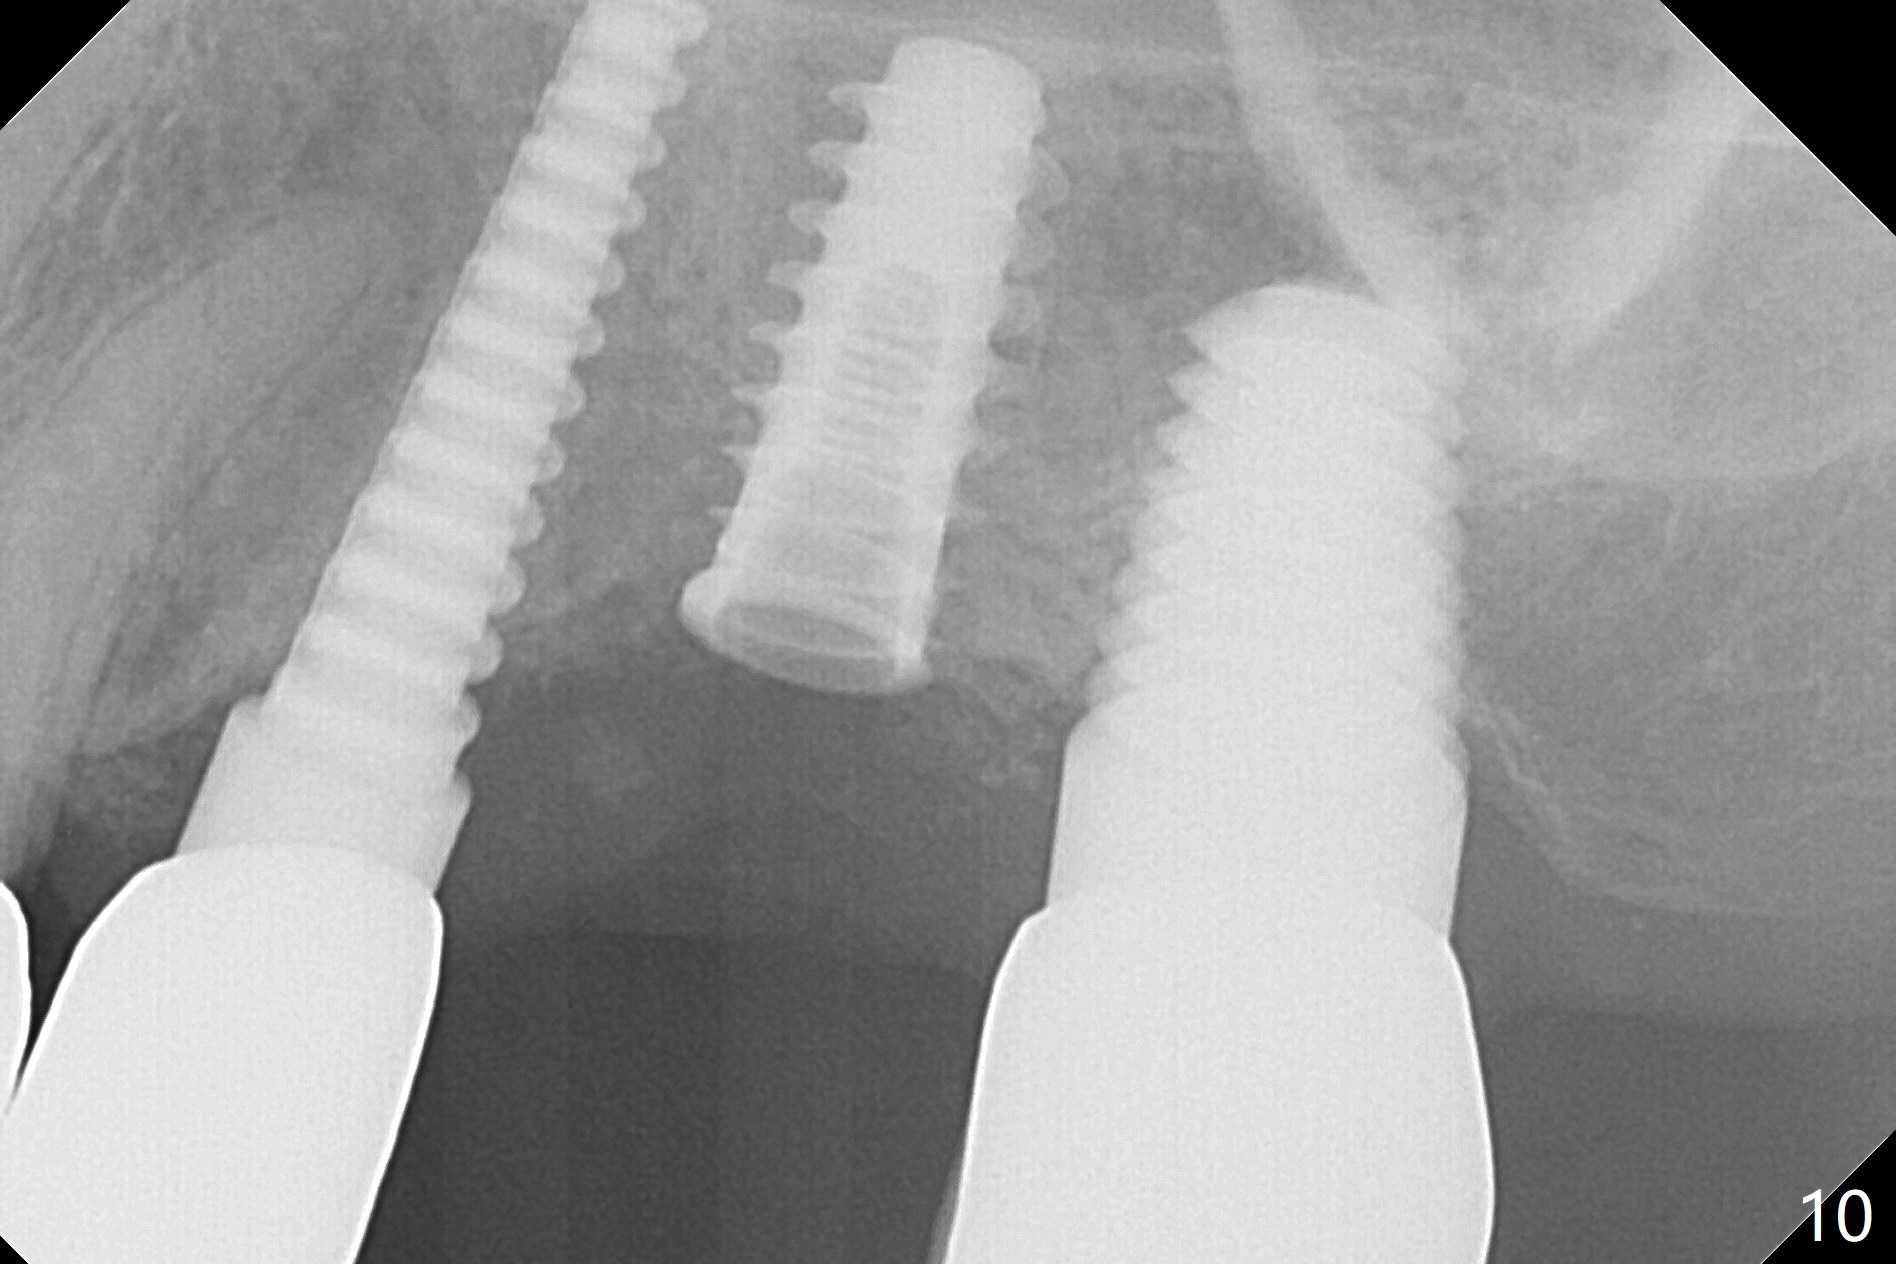

Initial osteotomy in the septum of the tooth #14 is 9 mm, approximately 2 mm from the sinus floor (Fig.1).  Subsequent osteotomy depth is 11 mm, followed by insertion of a 4.5x11 mm dummy implant (Fig.2).  After use of Magic Drill (MD) 4.8 mm for 9 mm, a 5x11 mm IBS implant is placed with sinus lift without additional bone graft (Fig.3 *).  In contrast, autogenous bone (from MD) and Vanilla Graft are meticulously placed in the remaining socket (+) before and after placement of a 6.5x5.7(2) mm abutment.  An immediate provisional is fabricated to close the sockets.  There is buccal tenderness 1-3 months postop.  There is distopalatal implant thread exposure.  A healing abutment (5.5x2 mm) is placed.  CT confirms thin buccal plate (Fig.4,5).  It appears that the implant should have been as palatal as possible.  The tenderness remains for the next 2 weeks.  When the healing abutment is removed, the implant seems to have been placed shallow, ~ 1 mm subgingival (Fig.6).  With local anesthesia, the implant is reversed to clean the coronal threads with Titanium brush and copious irrigation (Fig.7).  The implant is then placed ~4 mm subgingival (Fig.8) and slightly subcrestal (Fig.9,10).  It appears that the postop bone loss (Fig.9 *, as compared Fig.1,2) makes the implant look to be placed too shallow.  When the implant is being placed deeper, the buccal plate feels intact.  The early periimplantitis is apparently due to postop bone loss more than buccal placement, although certain degree of buccal bone resorption must occur.  A 6x4 mm healing abutment is placed.  Left facial swelling develops 2 days post implant elevation (Fig.11,12, as compared to preop (Fig.13)).  The left maxillary sinus cloud (Fig.12) appears to be a false positive finding, since the same feature exists prior to implant elevation (Fig.13).  Both sinuses look clear prior to implant elevation (Fig.14).  Amoxicillin switches to Augmentin and Flagyl, since the patient is reluctant to have the implant removed.  Finally the sinus infection is under control.  The patient feels left facial swelling 9 months postop (5 months post elevation) and reports left nasal discharge ~ 1 month earlier.  There is mild buccal plate tenderness.  The implant seems to be buccally placed (Fig.15,16), although there is no significant change radiographically (Fig.17).  The implant is removed with bone graft (Fig.18 *).  To avoid complication and failure, an immediate implant at the upper 1st molar should be short and placed deep.